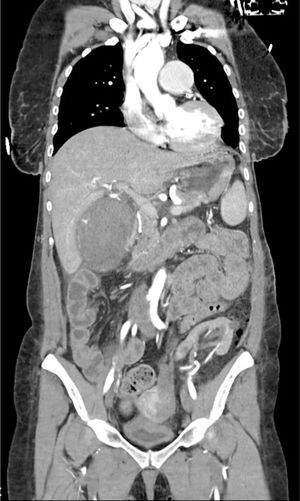

The patient is a 47-year-old female with a history of IgA nephropathy requiring a kidney transplant on 2 occasions and a right hemicolectomy due to intestinal perforation. In the immediate postoperative period after left nephrectomy due to a renal tumor, the patient presented hypovolemic shock secondary to necro-hemorrhagic cholecystitis, with active bleeding observed on CT (Figs. 1 and 2) performed due to suspected postoperative hemorrhage. Emergency cholecystectomy was performed, finding 500 cc of hemorrhagic content inside the gallbladder and active bleeding in the parietal peritoneum of the same, which was resolved after ligation of the cystic artery. The patient was discharged without complications.